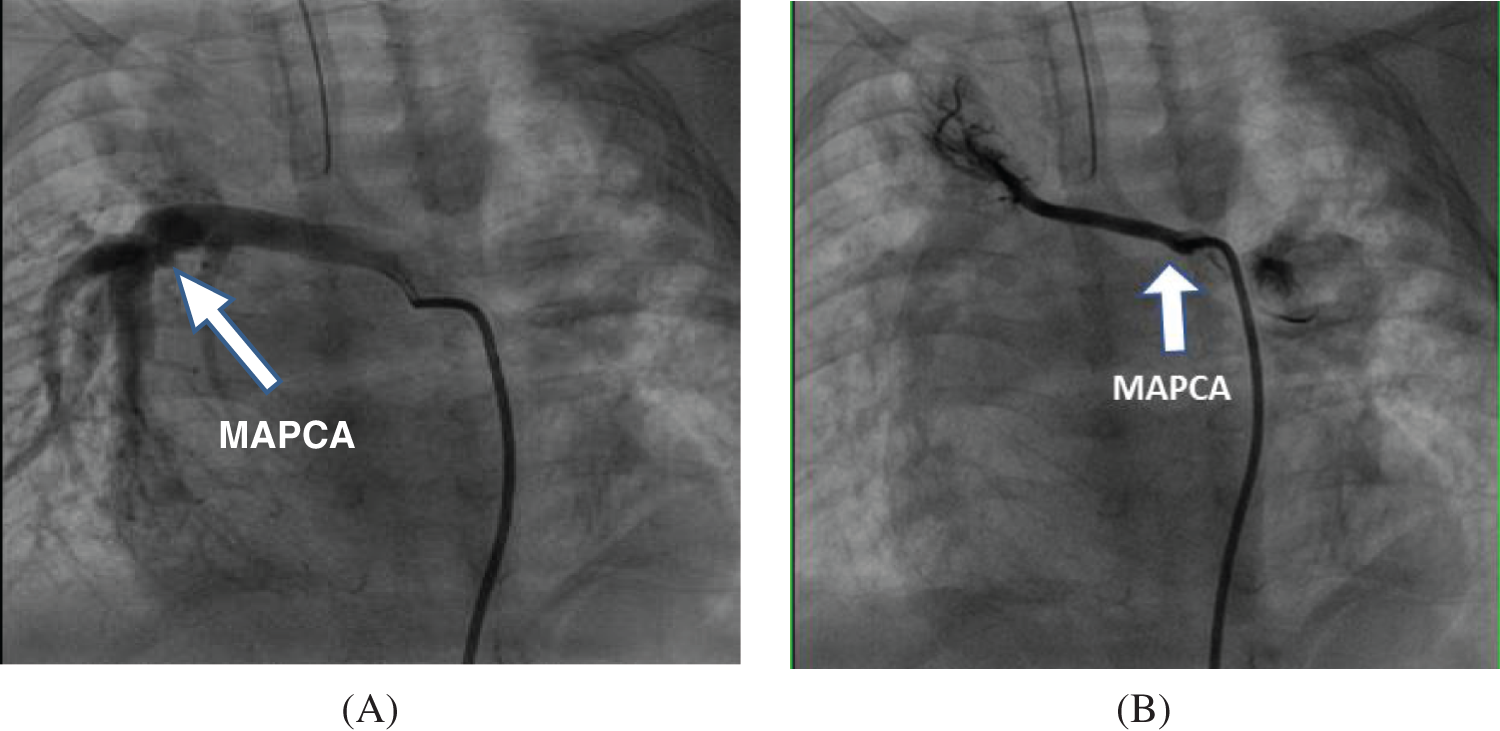

Collect preoperative cardiac color Doppler ultrasound, cardiovascular angiography and cardiac CTA imaging data, describe the number and anatomical distribution of MAPCAs, clarify the origin, size and morphology of MAPCAs, and evaluate the existence of native pulmonary artery and its development. According to the characteristics of MAPCAs, they are divided into “dendritic” distribution and “occlusive” distribution (see Fig. 1 for details). Based on this feature, it is divided into “functional collaterals” involving in blood gas exchange and non-functional collaterals. Functional MAPCAs were unifocalized during surgery, while non-functional collaterals were ligated during surgery. Fresh autologous pericardial patch was used to widen the opening following UF procedure, and Valved Bovine Jugular Vein Conduit (VBJVC) or Gore-Tex Valved Conduit (GTVC) was used for connection between RVOT and neo-pulmonary artery (neo-PA). We determined whether to close the ventricular septal defect or conduct VSD fenestration based on pRV/pAo and cardiac function status. Aortic cross-clamp time (ACCT), cardiopulmonary bypass (CPB) time, ICU duration, (ventilation) VT duration, postoperative stay length, and Neo-PA McGoon were collected. During the follow-up, echocardiography and electrocardiography were routinely performed.

Figure 1: Comparison of preoperative angiography results of different types of MAPCAs (A) “Dendritic”—The functional MAPCAs from the descending aorta are distributed in a “dendritic” shape, forming the lower right pulmonary vascular bed and participating in its “blood gas exchange” for intraoperative fusion; (B) “Occlusive”—The right subclavian artery MAPCAs are non-functional, distributed in an “occluded” state, do not participate in “blood gas exchange”, and undergo ligation during surgery

Among the 13 patients included in this study, 5 were type III pulmonary atresia and 8 were type IV, all of which were severe cases. The postoperative RVSP/LVSP was 0.47 ± 0.19, which was no different from the staged surgery reported in the literature [8]. Compared with conventional surgical methods, the “Selective unifocalization” proposed by us did provide the possibility of one-stage repair for subgroup of severe PA. Whether reconstruction of the native pulmonary artery (Rehabilitation) or unifocalization of MAPCA, the key is to rebuild and restore a complete pulmonary vascular bed as much as possible [9]. Based on the results of preoperative angiography, this study proposes “functional” pulmonary collaterals, which are unifocalized during the operation, and ligation of non-functional tortuous collaterals without obvious blood-gas exchange. Importantly, the key to the success of selective UF surgery is to accurately determine the functional MAPCA, that is, to find the collateral vessels involved in blood gas exchange. Normally, the anterior blood flow of the pulmonary artery is stable and the original vascular tissue develops into the bronchial artery. If the pulmonary artery is atresia and the forward blood flow disappears, the original tissue that should have developed into the bronchial artery develops into MAPCAs [10]. However, it cannot be concluded that MAPCAs and bronchial arteries are the same tissues [11]. MAPCAs should be accurately classified according to whether they participate in blood gas exchange function [12]. Generally, their morphology is more similar to nature pulmonary blood vessels. Different from other literature [13], We proposed that pulmonary collaterals with “blood gas exchange” should be evaluated based on the characteristics of the morphology and distribution of blood vessels in the lung. That is, the “dendritic” distribution is more similar to the nature pulmonary blood vessels, which are functional MAPCA, and the “occlusive” distribution belongs to non-functional collaterals that do not participate in blood gas exchange. The former undergoes unifocalization during surgery, and the latter should be ligated.